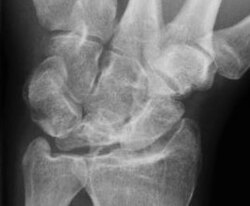

Die Lunatummalazie (syn. Mondbeinnekrose, Kienböck-Krankheit) ist der weitgehende Untergang (Nekrose) des Mondbeins im Handgelenk. Sie ist schon lange bekannt, konnte aber erst mit der Entdeckung der Röntgenstrahlung anatomisch zugeordnet werden. Die erste Beschreibung erfolgte 1910 durch den österreichischen Röntgenarzt Robert Kienböck (1871–1953), nach dem die Erkrankung im anglo-amerikanischen Sprachraum benannt ist. Sie gehört zu den aseptischen Knochennekrosen.

Die Nekrose entwickelt sich ohne sonderliche Schmerzen und kann jahrelang unentdeckt bleiben. Schmerzen in der Streckseite des proximalen Handgelenks führen zur Röntgenuntersuchung, die häufig und in einem fortgeschrittenen Stadium eine Blickdiagnose ermöglicht. Die Magnetresonanztomographie und die Computertomographie können initial zur Diagnosesicherung beitragen. Entwickeln können sich ein Kraftverlust der betroffenen Hand und deutliche Bewegungseinschränkungen des Handgelenks.

| Dorsopalmare Röntgenaufnahme vom linken Handgelenk eines 58-jährigen Druckluftarbeiters: Lunatummalazie | Überlassene CD beim Patienten | Dr. med. Ulf Schneider, Orthopäde in Anklam | Datei:Lunatummalazie AP.jpg | |